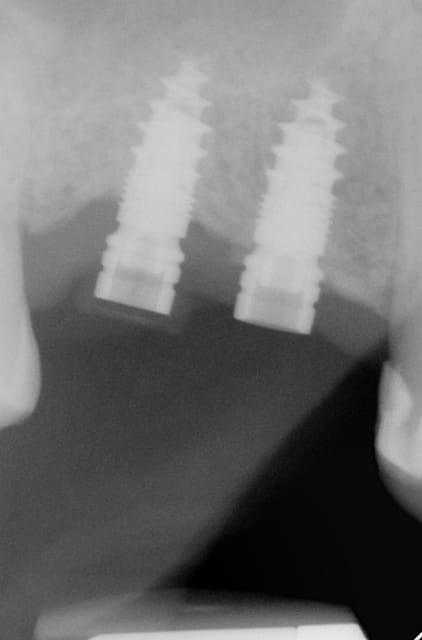

Pour ceux que ca interessent, et parce qu on a m a demandé des cas supplémentaires dans le sujet 23 implants rehabilitation totale, voici un autre cas d implantation immédiate avec la technique minimalement invasive et condensation grace aux forets.

Le patient a reçu un traitement il y a dix ans dans le maxillaire et dans le 4eme quadrant.Comme on peut le voir j´ai du extraire quelques dents au maxillaire: 35 37 et 45.

Le septum de la 37 a été foré avec un foret conique 3 faces.

J ai planté à 60 Ncm sans fracturer le septum.Juste après l opération , les prep caps en zircon ont été cémenté.La restauration définitive 34 jusqu` à 37 été fixé 2 semaines après l implantation avec implantlink (detax). Après un an, le bridge a été retiré facilement pour voir l´état de la gencive et faire une radio de contrôle.On la re ossifiction est satisfaisante et que la gencive "aime" le zircon.

Le bridge a ensuite été recémenté sans correction nécessaire du bridge.